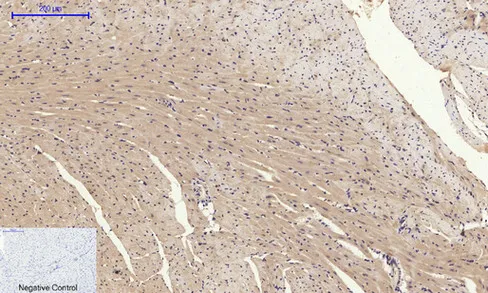

Glut4 Rabbit Polyclonal Antibody

Cat: APRab11504